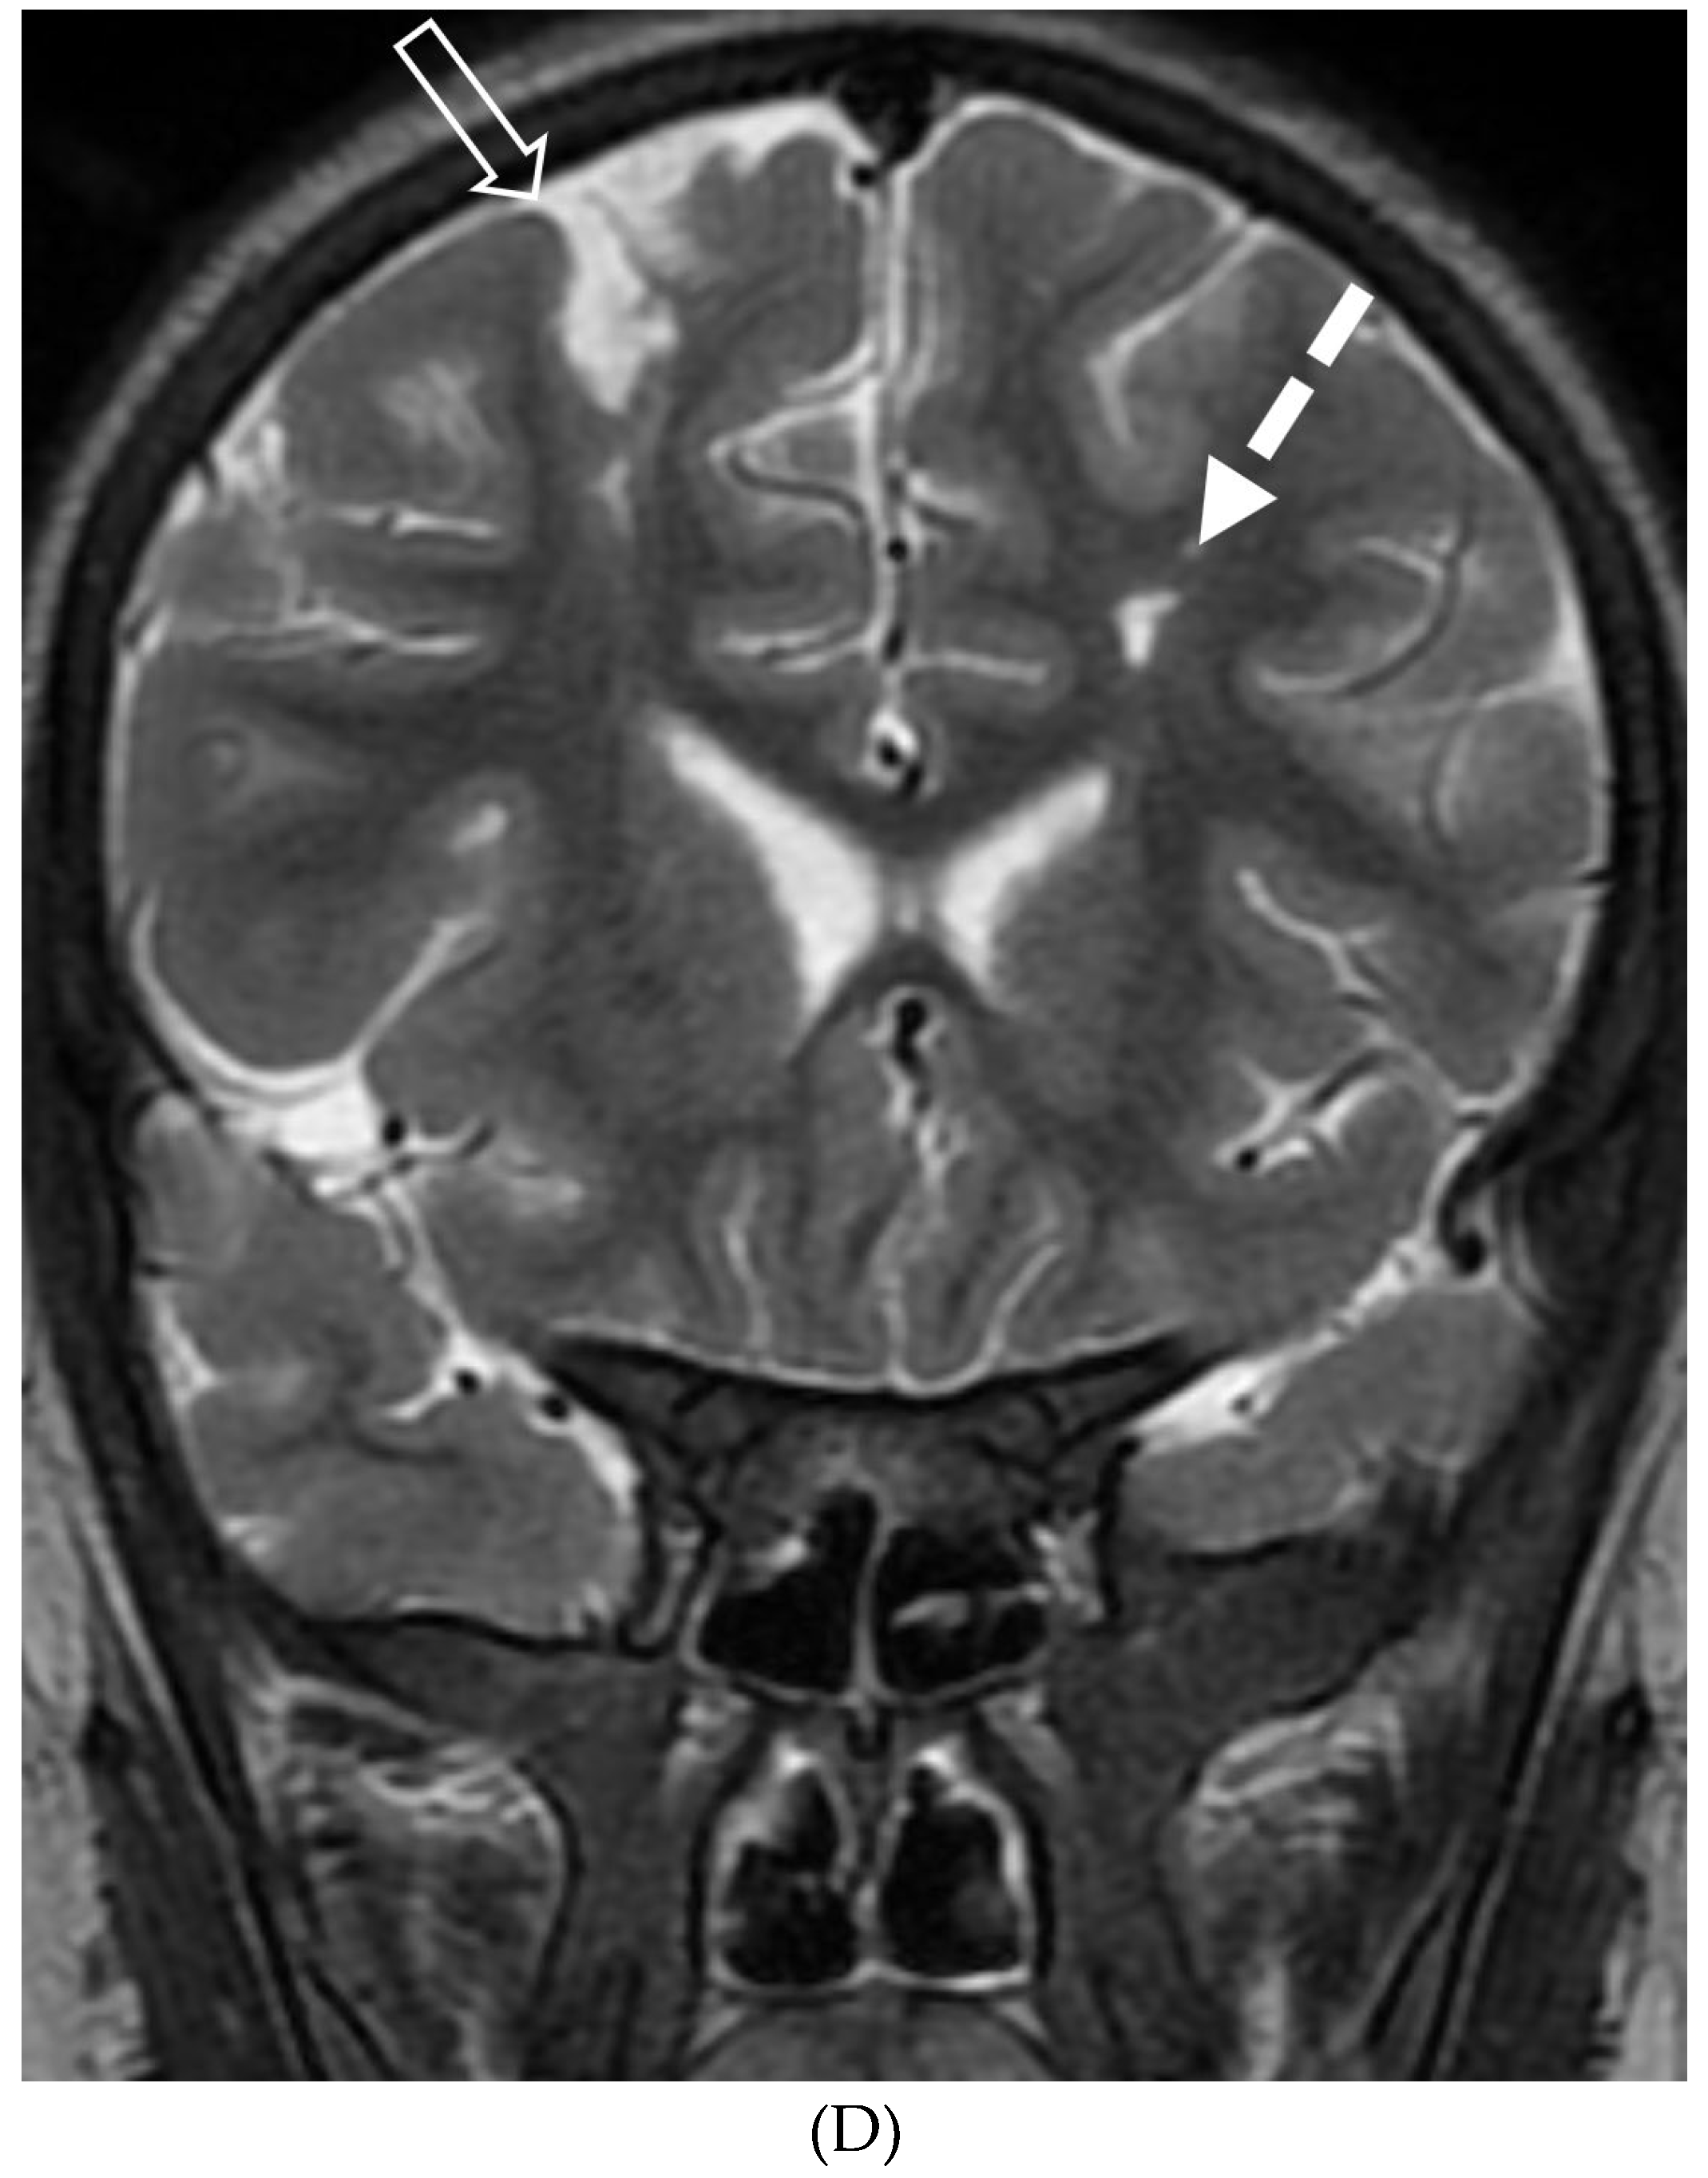

- Horie N, Morikawa M, Nozaki A, Hayashi K, Suyama K, Nagata I. "Brush Sign" on susceptibility-weighted MR imaging indicates the severity of moyamoya disease. AJNR Am J Neuroradiol. 2011 Oct;32(9):1697-702. Epub 2011 Jul 28. PMID: 21799039; PMCID: PMC7965393. [CrossRef]

- Ohta T, Tanaka H, Kuroiwa T. Diffuse leptomeningeal enhancement, "ivy sign," in magnetic resonance images of moyamoya disease in childhood: case report. Neurosurgery. 1995 Nov;37(5):1009-12. PMID: 8559324. [CrossRef]

- Maeda M, Tsuchida C. "Ivy sign" on fluid-attenuated inversion-recovery images in childhood moyamoya disease. AJNR Am J Neuroradiol. 1999 Nov-Dec;20(10):1836-8. PMID: 10588105; PMCID: PMC7657767.